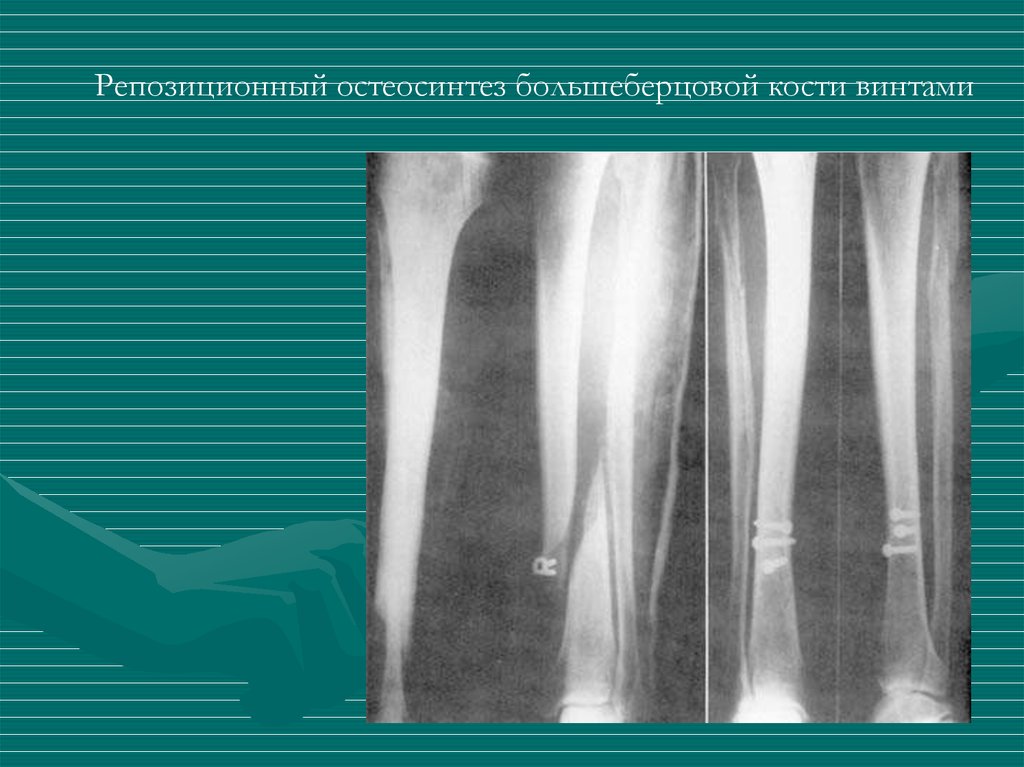

Репозиционный остеосинтез большеберцовой кости винтами